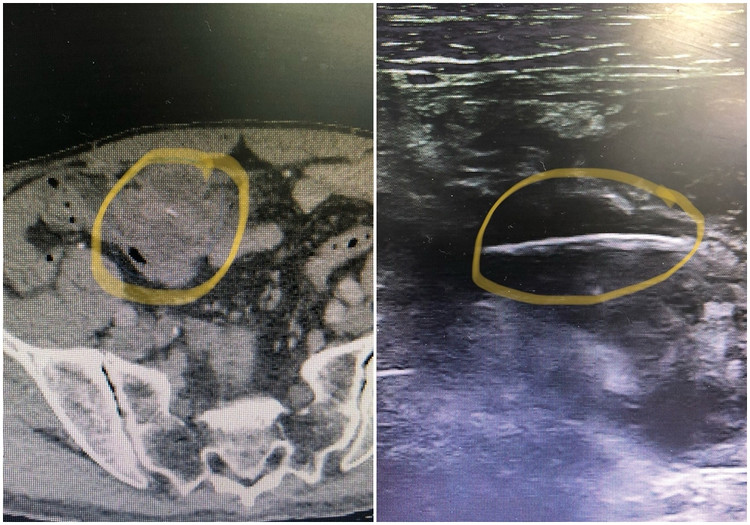

| Hình ảnh xương cá đâm thủng ruột bệnh nhân - Ảnh BVCC |

Tại Bệnh viện Đa khoa tỉnh Quảng Ninh, qua kết quả siêu âm, chụp cắt lớp vi tính, các bác sĩ phát hiện gần đại tràng có ổ dịch, bên trong có dị vật hình que dài. Các bác sĩ chẩn đoán bệnh nhân bị viêm phúc mạc do dị vật xuyên thủng đại tràng và chỉ định phẫu thuật nội soi cấp cứu lấy dị vật.

Kíp phẫu thuật khoa Ngoại do bác sĩ CKII Phạm Việt Hùng, Trưởng khoa cùng các cộng sự phối hợp cùng bác sĩ CKI Phạm Trung Đức, Phó khoa Gây mê hồi sức thực hiện. Qua 3 troca ở ổ bụng, phẫu thuật viên đưa dụng cụ nội soi kiểm tra vùng giữa đại tràng ngang có khối viêm lớn được mạc nối bọc lại, bóc tách ra có nhiều dịch mủ, ở giữa là dị vật mạnh xương cá dài 3cm đâm xuyên thành ruột.